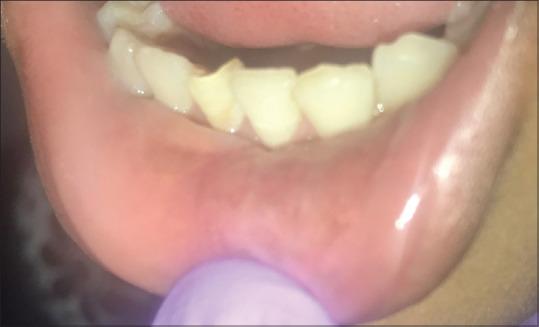

Tuberculosis is a chronic granulomatous disease which affects the lungs in majority of the cases. Oral manifestations of tuberculosis (TB) are seen both in primary and secondary stages of the disease but are most commonly associated with secondary TB. Primary oral TB is a rare entity and thus may pose a diagnostic challenge. This case reports isolated primary TB of the lower lip associated with an intraoral long-standing nonhealing ulcer present in a 12-year-old child. The diagnosis was confirmed by histopathological, hematological, and radiographic investigations. The lesion resolved with anti-tubercular treatment regimen. The case highlights the importance of clinician awareness toward oral lesions, which may present themselves without any symptoms and/or signs of systemic disease.

结核病是一种慢性肉芽肿性疾病,大多数情况下会累及肺部。结核病的口腔表现可见于疾病的原发和继发阶段,但最常与继发性结核病相关。原发性口腔结核是一种罕见的病症,因此可能带来诊断挑战。本病例报告了一名12岁儿童下唇孤立性原发性结核,伴有口腔内长期不愈合的溃疡。通过组织病理学、血液学和影像学检查确诊。病变经抗结核治疗方案后消退。该病例凸显了临床医生对口腔病变提高认识的重要性,这些病变可能在没有任何全身疾病症状和/或体征的情况下出现。